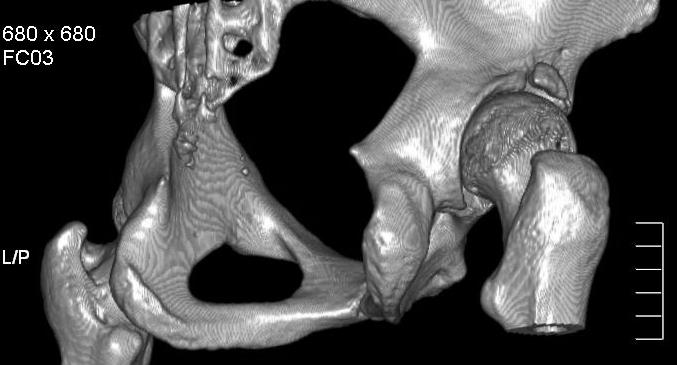

Добавляю снимков для "информационной поддержки принятия решения" (ну, нравится мне это выражение )). Поступило предложение выполнить артроскопию для оценки сохранности хряща. Насколько это необходимо?